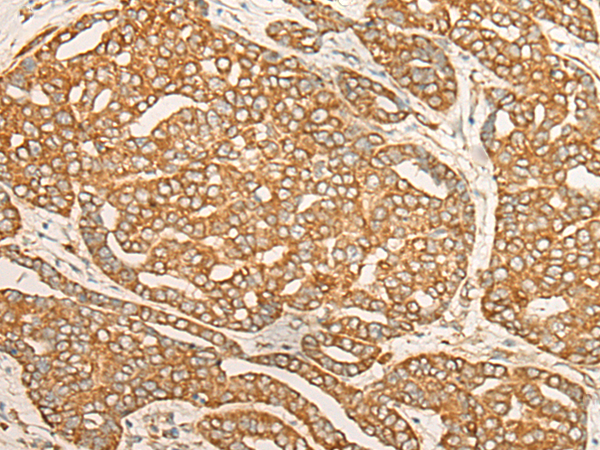

IHC positive control: |

Human liver cancer |

IHC Recommend dilution: |

30-150 |